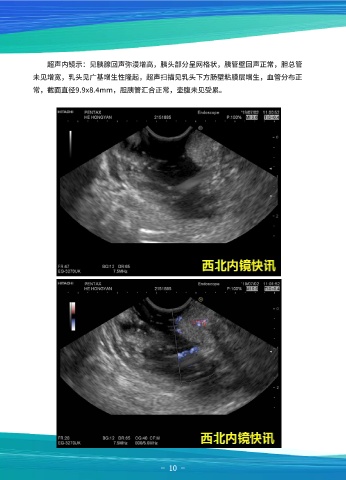

超声内镜示:见胰腺回声弥漫增高,胰头部分呈网格状,胰管壁回声正常,胆总管

未见增宽,乳头见广基增生性隆起,超声扫描见乳头下方肠壁粘膜层增生,血管分布正

常,截面直径9.9x8.4mm,胆胰管汇合正常,壶腹未见受累。